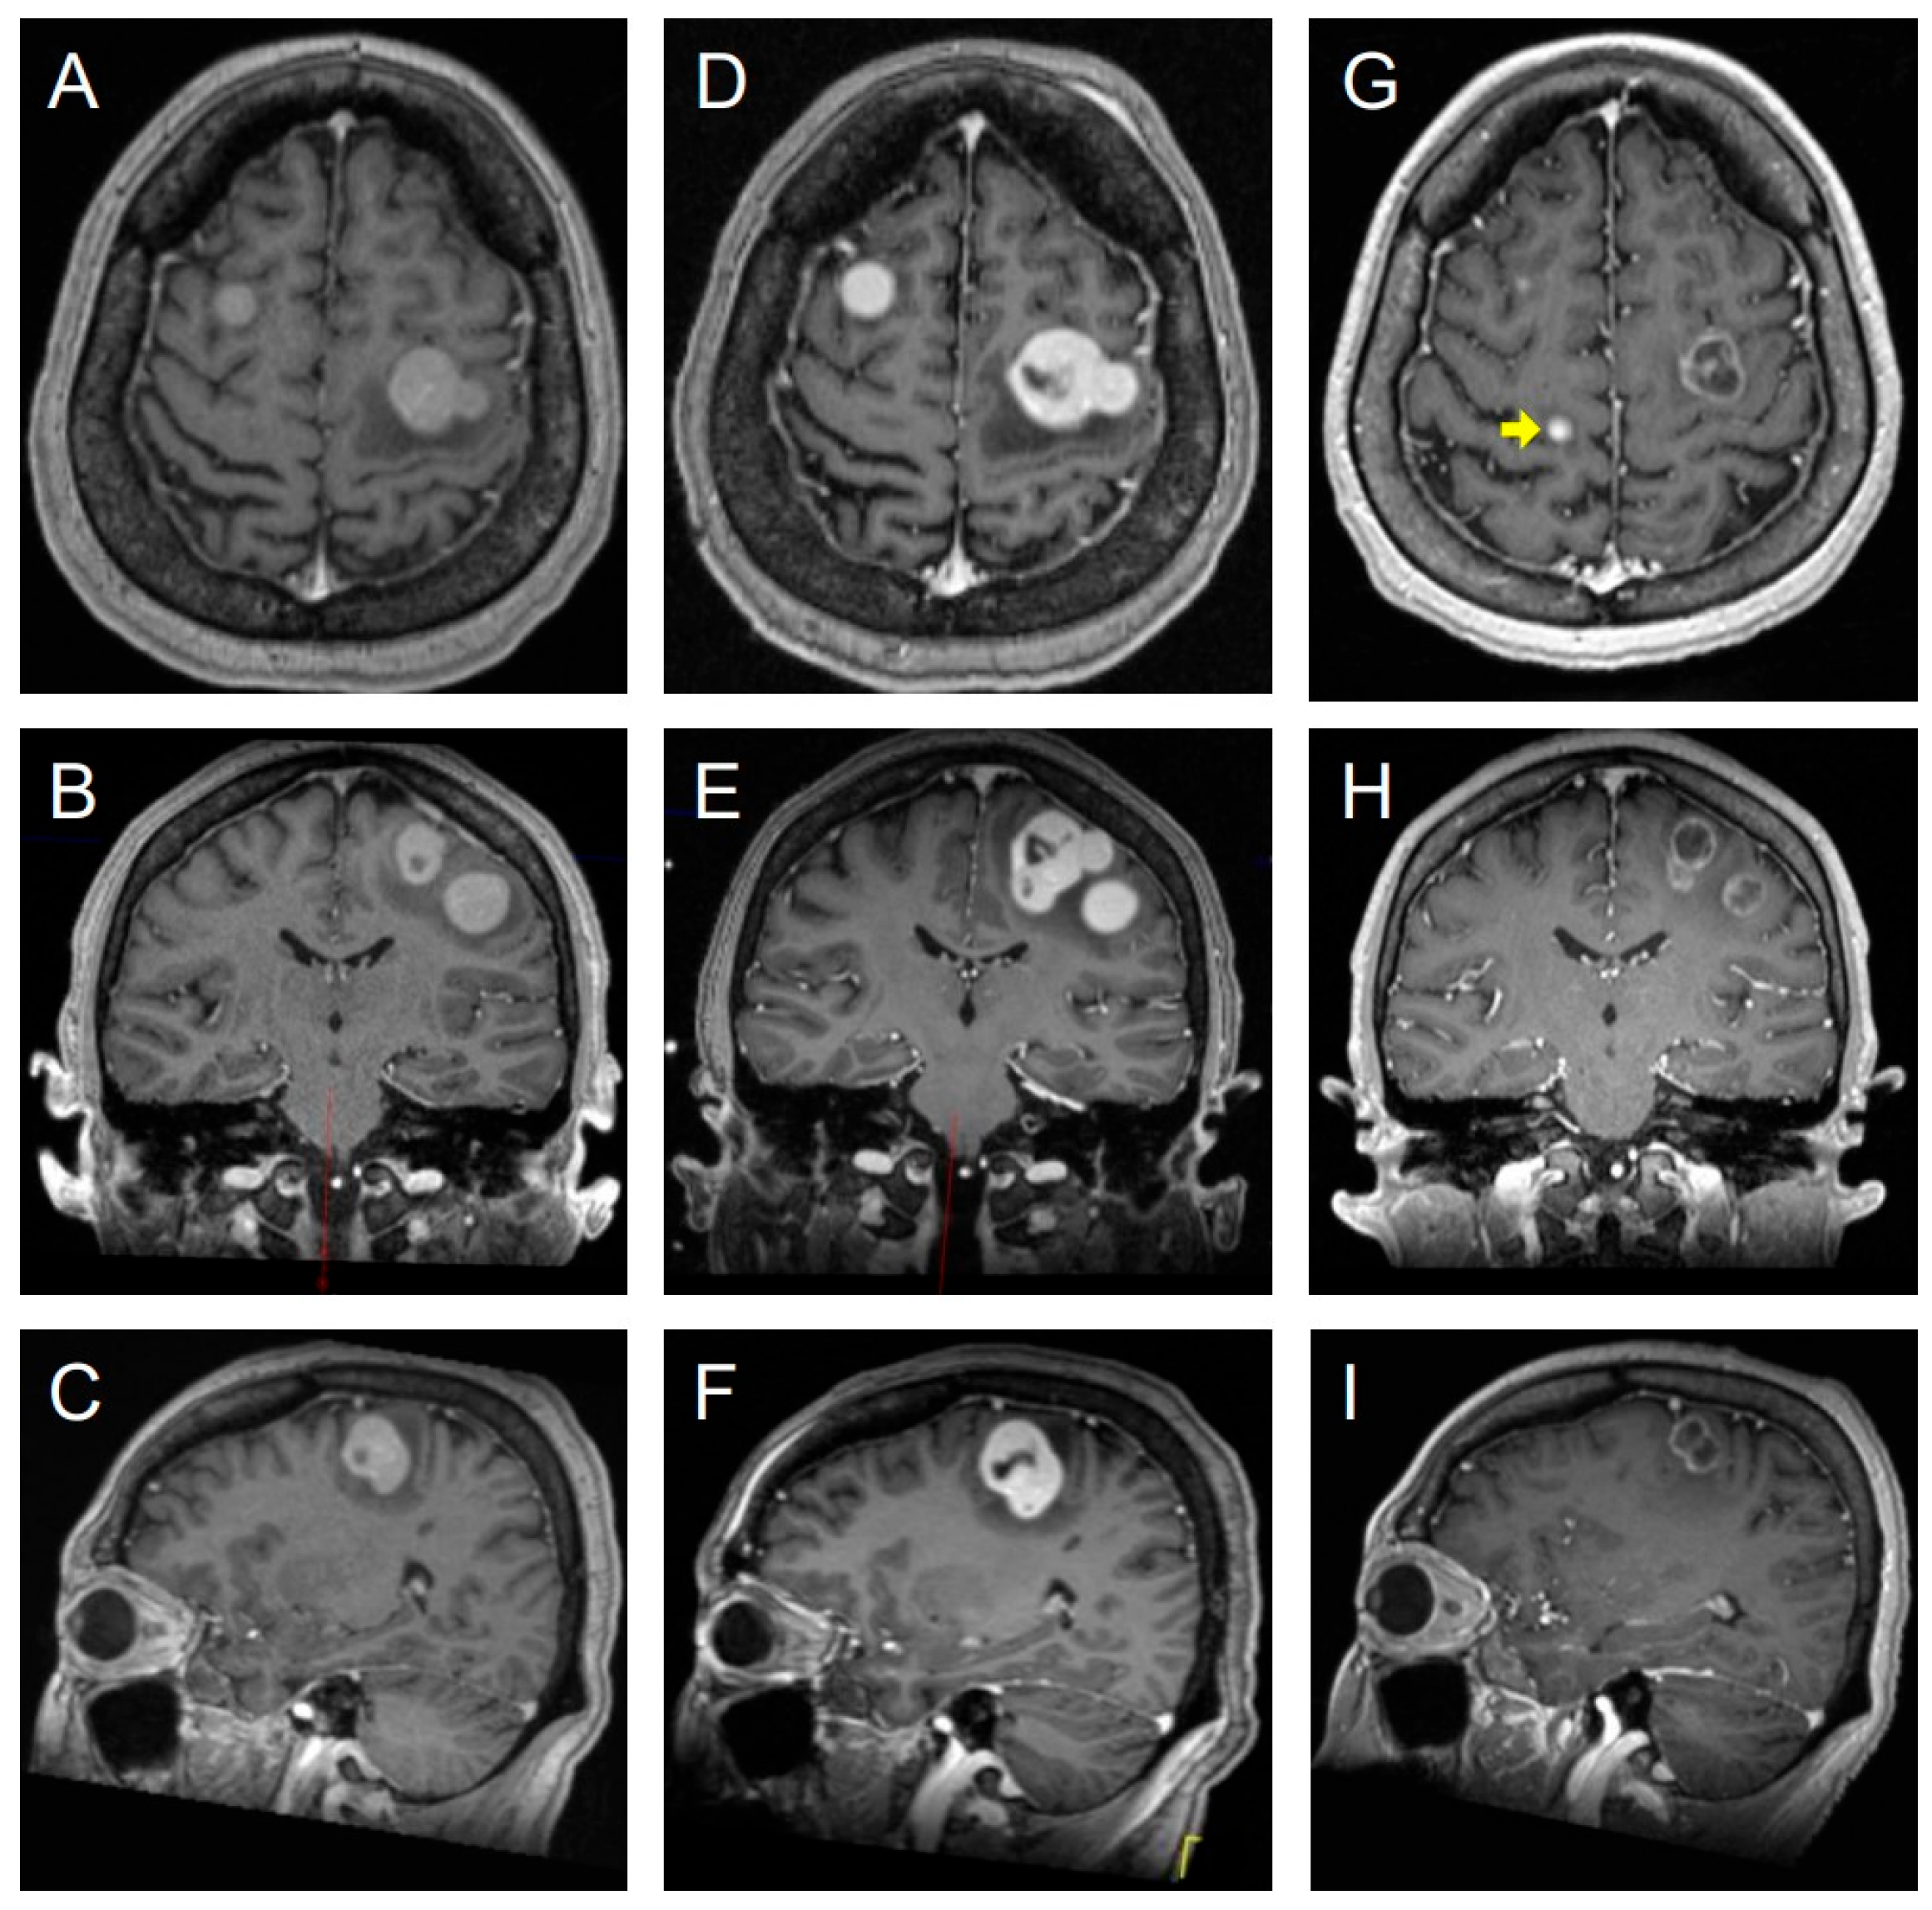

3.8. Illustrative Case